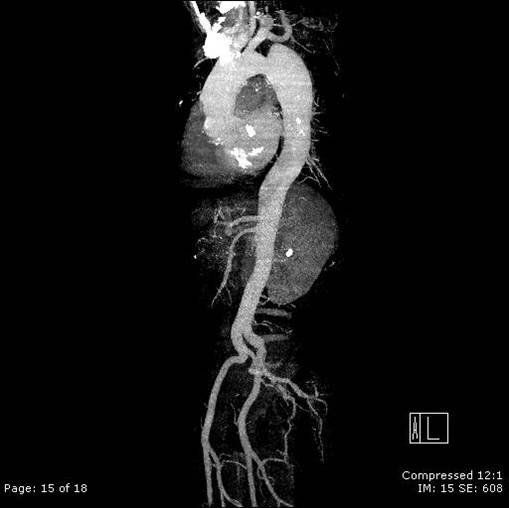

Dissecção de aorta toraco-abdominal.

Após o diagnóstico de dissecção é necessário localizá-la, definindo o envolvimento de ramos aórticos, e identificar fatores agravantes relacionados com a própria aorta e os seus ramos e órgãos relacionados.

A. Localização:

A localização é o principal fator determinante do tratamento. Habitualmente o acometimento da aorta ascendente (tipo A de Starford) indica tratamento cirúrgico pelo risco de complicações fatais, enquanto dissecções com inicio distal à artéria subclávia esquerda (tipo B de Stanford) usualmente tem tratamento conservador na ausência de complicações.

Na dissecção tipo B, o flap intimal habitualmente localiza-se logo após a emergência da artéria subclávia esquerda. É importante localizar os sítios de laceração porque a cirurgia e os procedimentos de colocação de prótese objetivam a oclusão das lacerações para induzir a formação de trombo na luz falsa.

C. Definição da origem dos ramos aórtico:

A tomografia multislice tem resoluções espacial e de contraste confiáveis para estudo do suprimento dos ramos aórticos, ou seja, se originários da luz verdadeira ou da luz falsa.